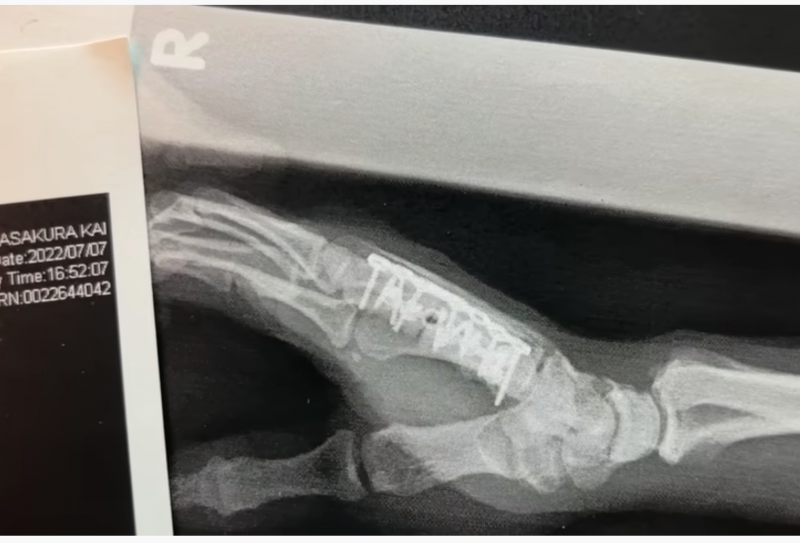

手術後のレントゲン写真。手の甲が真っ直ぐになった。手術した部分には金属プレートと15本のボルトが入った手術前、右手が開かない状態を説明(KAI Channelより)